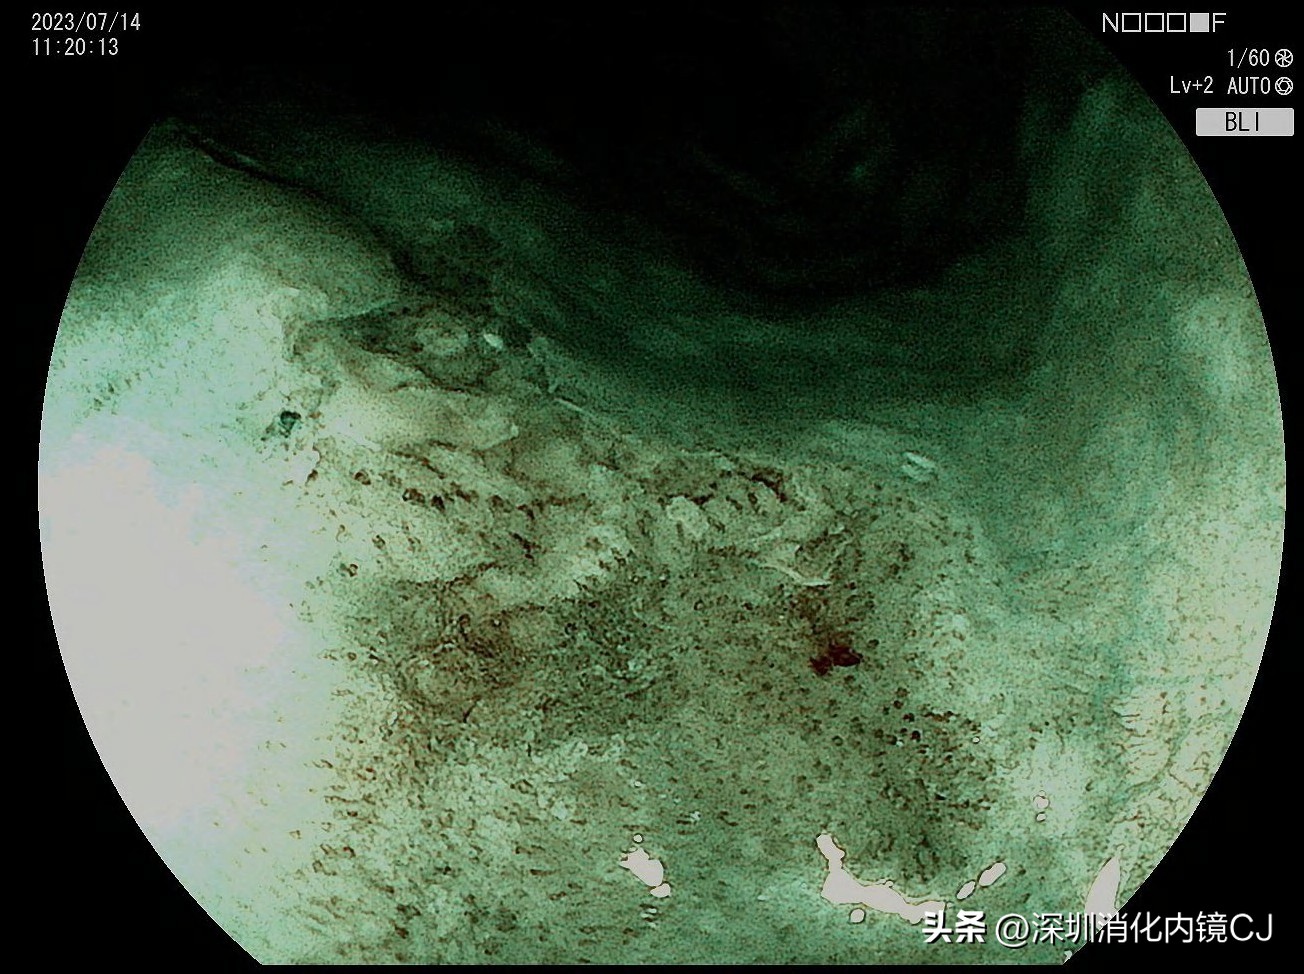

BLI模式见IPCL Type B1型

BLI放大模式,病变茶褐色,IPCL呈Type B1型,考虑早期食管癌